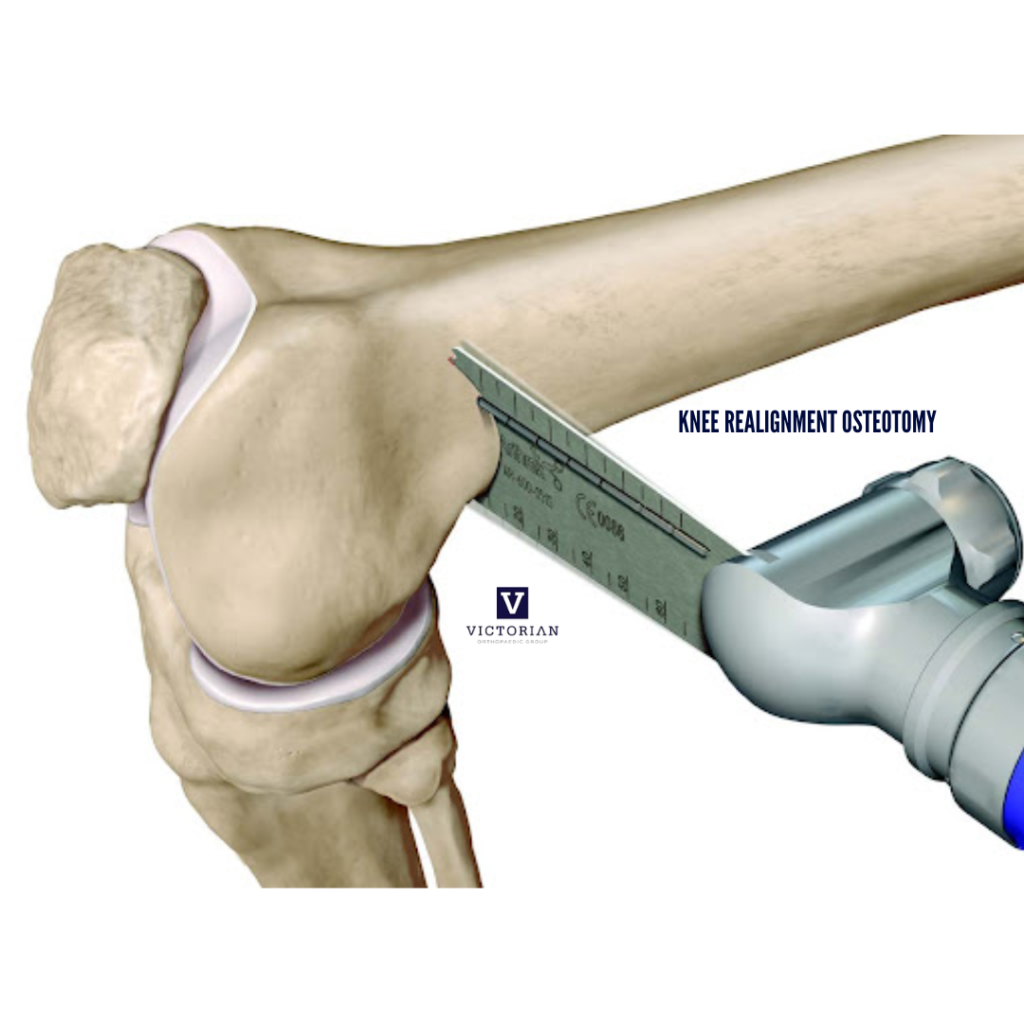

Knee Realignment Osteotomy